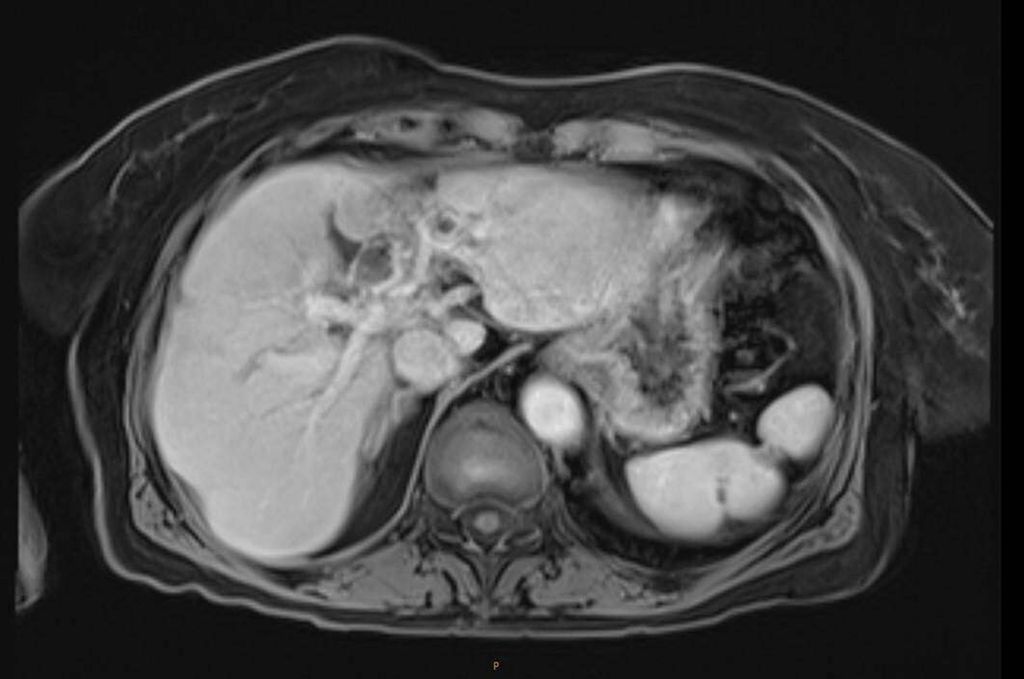

In der durchgeführten Staging-CT zeigte sich ein partielles Ansprechen (PR) mit Tumorgrößenreduktion von 49mm auf 33mm, die Lymphknoten blieben unverändert. Die Tumormarker sanken (AFP: 150, Ca19-9: 65). Aufgrund der persistierenden Diarrhö und des Verdachts auf einen Mischtumor erfolgte eine Umstellung der Therapie auf Cisplatin/Gemcitabin/Bevacizumab, wobei Gemcitabin ab Zyklus 2 wegen Fatigue auf 75% reduziert wurde und Cisplatin ab Zyklus 3 aufgrund von Ototoxizität abgesetzt werden musste. Nach vier Zyklen zeigte die MRT ein weiteres partielles Ansprechen (19×21mm), die Lymphknoten waren unverändert, die Tumormarker normalisierten sich erstmals.

Im weiteren Verlauf traten rezente embolische, bihemisphärische Infarkte auf, ätiologisch als kardioembolisch bewertet. In der letzten MRT, viereinhalb Jahre nach Erstdiagnose, zeigten sich postradiogene Parenchymveränderungen, jedoch kein Hinweis auf ein Lokalrezidiv.

Bildgebend können sich Mischtumoren wie ein HCC-iCCA-Gemisch imponierend darstellen, wie ein typisches HCC oder aber ein typisches iCCA aussehen oder sich unspezifisch darstellen. Bildgebende Hinweise auf Mischtumoren bestehen bei verschiedenartigem Kontrastmittelverhalten innerhalb eines Tumors (im Verlauf zunehmende Anreicherung, Anreicherung mit Wash-out, Anreicherung ohne Wash-out oder Hypovaskularisierung), vaskulärer Invasion und Gallengangsbeziehungen. Die Kombination erhöhter Tumormarker (AFP und Ca19-9) kann einen Hinweis liefern, ist aber nicht beweisend.